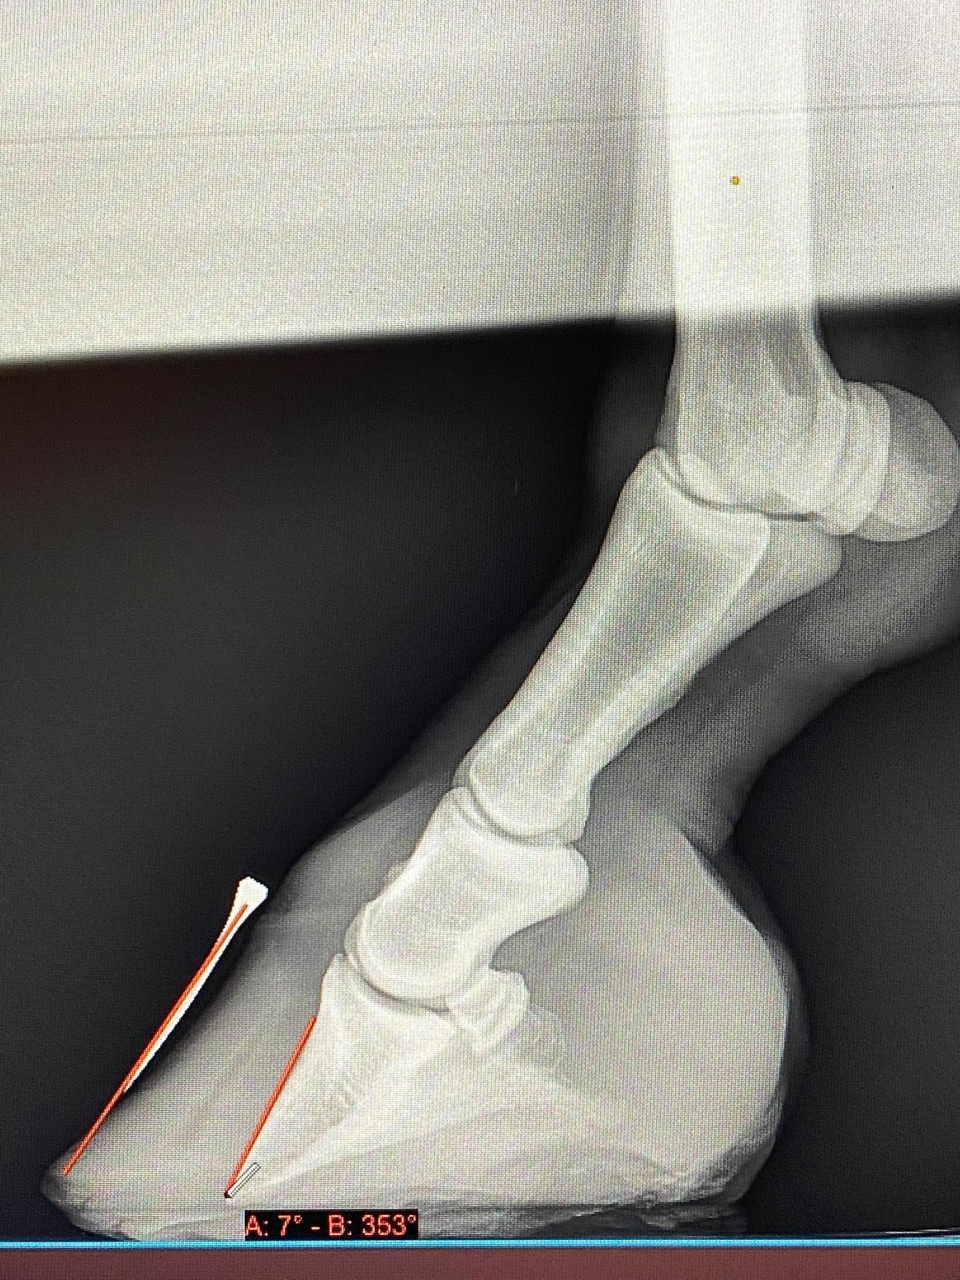

| Dire merci | dejavu c'est gentil de prendre des nouvelles alors aujourd'hui elle est bcp couchée car hier elle a eu une grosse journée : trajet aller retour vt pds glucose, insuline dpip les radios sont cata, mais on s'en doutait rotation + effondrement le véto qui est aussi maréchal m'a dit qu'on peut ferrer, fers à l'envers + semelle, mais vu comme elle se déplace super bien en chaussures, il la laisserait guérir en chaussures. par contre il me dit que baisser les talons tire sur le tendon, mais vu que c'est la seule solution pour réaligner j'ai du mal à comprendre. Je lui ai dit que ça allait être fait très progressivement. elle a été parée en plein crise, et ça l'avait tout de même soulagée ! les talons sont à 2,5, avec l'angle de rotation il faudrait progressivement descendre à 1,9 / 2 cms ça je vais voir avec mon pareur j'hésite fortement à appeler mon ancien mf je sais qu'il a des fourbus à soigner chez lui dans son manège ,que ferrer ou clogs serait LA solution, mais dans ce cas il faudrait faire des radios à chaque parage..... et puis, MUesli me dit quand même qu'elle est super à l'aise en chaussures..... ou alors elle mord vachement sur sa chique ! en aliments elle a des cmv, probiotiques et ses plantes spécial cushing mais elle ne reçoit plus de prascend : j'ai arrêté pour faire le bilan sanguin. tout ça dans du préalpin réhydraté et elle a son foin trempé. je suis tombée sur ce site : comme c'est un peu le thème de ce post ! Il y a le taux de fructane en temps réel pour la Belgique ! je ne sais pas si le site géolocalise et qu'il donne les taux pour la France mais je trouvais ça super il donne aussi un calculateur de ration et on peut y acheter des pierres à lécher enrichies en magnésium ! je vais pas prendre pour le moment j'ai plus de sous lol mais je trouve ça super intéressant même pour mon jeune cheval : sur le site il n'a besoin de rien d'autre que son herbe et son foin.... je le sais Tessa me l'a dit, tu me l'as dit, dushara me l'a dit, les aliments c'est un commerce. j'aime bien donner une ration : ils rentrent tout seuls le soir, et ils peuvent y prendre leurs cmv facilement donc je vais continuer mais simplement au préalpin et aliment qui ne sert à rien du genre care 4 life ou fiberforce et mon jeune va finir ses sacs d'aliments croissance tranquillement, il n'a vraiment pas grand chose je n'étais pas une acharnée des rations non plus hein ! c'était très peu comme je l'ai dit plus haut. je suis une maman : mon besoin de nourrir est viscéral ![]() ![]() je ne mets que 2 clichés je pense que c'est le même pied mais en gros yen a un à 7 et un à 8 lien pour le taux de fructane en temps réel, j'utilise un traducteur Lien et lien sur l'alimentation, Lien |

DéconnectéDire merci | Super qu'il accepte de la laisser guérir en hipposandales, c'est LE meilleur moyen. Si tu ferres, en dehors du fait que ce sera douloureux, impossible de corriger régulièrement par le parage, ce qu'il FAUT toutes les deux à quatre semaines et en effet baisser les talons petit à petit... Je m'énerve à chaque fois que j'entends cette histoire du tendon qui tirerait sur la phalange et augmenterait la bascule.... C'est peut-être un tout petit peu le cas MAIS: imagine: on ferre en surélevant le talon pour soi-disant diminuer cette traction et que se passe-t-il? La pointe de la phalange appuie en plein sur une sole déjà trop fine et fragilisée jusqu'à la percer... D'autre part un tendon c'est pas un élastique, c'est raccroché à un muscle et cemuscle il va assez rapidement faire son boulot et se raccourcir pour "retendre" le tendon... donc on va avoir une situation empirée avec un muscle crispé plus les compensations, un tendon qui va continuer de tirer sur l'os, un pied ferré dans une position désatreuse et une connexion lamellaire endommagée qui va se retrouver dans l'impossibilité de se rétablir et d'offrir une résistance à ce mouvement de rotation... Car si la phalange se retrouve ainsi ce n'est pas à cause du tendon mais bien parce que la connexion lamellaire a lâché.... C'est ELLE qu'il faut soulager et remettre en état. Quant au fructane, c'est dépassé en ce sens que ce n'est pas le fructane le responsable. Mais ce genre de site est utile en ce sens que si le taux de fructane augmente en fait il y a augmentation de tous les glucides de l'herbe, on peut donc l'utiliser comme une sorte de thermomètre ;-) La guérison sera longue mais vous allez y arriver. |